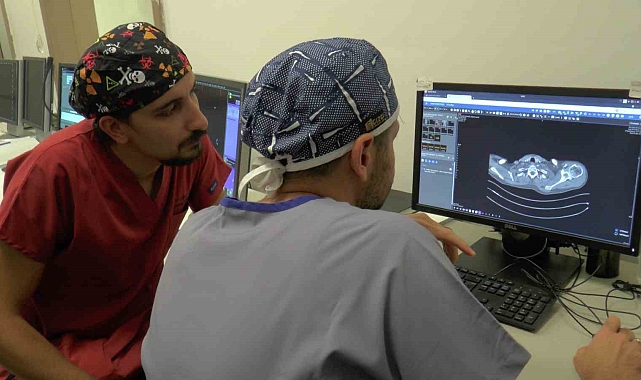

Kayseri'de yaşayan Behçet hastası Osman Turan, akciğerlerinde meydana gelen ve kendisinde ölüm korkusuna sebep olan kanamalardan Kayseri Şehir Hastanesi'nde uygulanan embolizasyon işlemi sayesinde kurtuldu.Behçet hastalığı bulunan Osman Turan'da hastalıkta nadir yaşanan bir durum görüldü. 'Hemoptiz' olarak adlandırılan durum sonucunda akciğerlerinde meydana gelen kanamadan dolayı ağzından ve burnundan kan gelen Turan, birçok kez kanamalarından dolayı yoğun bakımda yattı. Daha sonra Kayseri Şehir Hastanesi Girişimsel Radyoloji Bölümü'ne sevk edilen Osman Turan, hastanede uygulanan embolizasyon yöntemi ile kanamalarından ve yaşadığı ölüm korkusundan kurtuldu.Yaşanan durumun nefes sıkıntıları oluşturup arrest denilen ani kalp durmasına kadar gidebileceğini söyleyen Kayseri Şehir Hastanesi Girişimsel Radyoloji Bölümü'nden Dr. Sinan Karatoprak, "Behçet hastalığı Asya ülkelerinde ve bizim ülkemizde sık görülen romatolojik bir hastalıktır. Genellikle ağızda yaralar, genital bölgede ülserler ve nadiren de damar tutulumlarıyla seyreden romatolojik bir hastalıktır. Osman bey uzun süredir Behçet tanısı almış ve takipli olan bir hasta, ağzından akciğer kaynaklı kan gelmesi şikayeti ile göğüs hastalıklarına başvurmuştu. Orada çekilen tomografisinde kalpten kirli kanı temizlenmek üzere akciğere taşıyan damarda bir anevrizma dediğimiz baloncuk tespit edilmesi üzerine tedavi amaçlı bize yönlendirildi. Bu şekilde de işlem kararı verdik hastayla. Behçet hastalığında nörolojik tutulum ve vasküler tutulum nadir görülmekte. Özellikle Osman beyde olan durum hastalıkta yüzde 1 olarak tanımlanmıştır literatürde. Polimer arter anevrizma hastalarda en sık şikayet akciğerden kan gelmesi şikayetidir. Hemoptiz olarak adlandırıyoruz biz bu durumu ve bu durum aşırı miktarda kanama olduğu zaman hastada nefes sıkıntıları oluşturup arreste kadar gidebilir ki Osman beyde de geçmişte öyle bir durum olmuştu" dedi.Girişimsel Radyoloji Bölümü'nden Dr. Oğuz Aslan da Behçet hastalığı olanların kanama durumunda akciğer atardamarlarında bir anevrizma olabileceğini akıllarında bulundurması gerektiğini söyleyerek, "Osman bey bize göğüs hastalıkları tarafından yönlendirildi. Kendisinin Behçet hastalığı tanılı, tekrarlayan akciğer kaynaklı kanamaları mevcuttu ve pulmoner anevrizma dediğimiz bir baloncuk mevcuttu Behçet hastalığında sekonder olarak nadir gelişen bir durum olarak. Hastamıza bu anevrizmanın kapatılabileceğini ve işlemin nasıl olduğunu, risklerini anlattık. Kendisi de düşündü ve tedavi olmaya karar verdi. Öylelikle bir teşhise dair anjiyoya aldık kendisini. Tedavi planımızı belirledik ve ikinci bir seansta kendisine bu büyük damarları tıkamakta kullandığımız vasküler tıkaçlar dediğimiz materyaller ile anevrizmasını kapattık. Anevrizma kapatmanın aslında birçok yöntemi var ama hastamızın besleyici damarı çok büyük olduğu için bunları daha büyük damarları tıkamak için kullandığımız materyalleri kullandık. Bir gün serviste yattı ve ertesi gün taburculuğunu sağlamış olduk. Bizim gördüğümüz hastaların çoğu Behçet hastası ve bu hastaların yüzde 1-2'sinde görülebiliyor bu komplikasyon. Embolizasyon işlemi sonrasında hastamızın bu mevcut durumu tamamen kapandığı için en azından bu anevrizma özelinde ekstra bir akciğer kanaması hemoptizi ihtimali ortadan kalkmış oldu. Şöyle söyleyebiliriz; Behçet hastalığı tanısı olan hastaların öksürükle ağzından kan gelmesi durumunda akciğer atardamarında bir anevrizma olabileceği akılda bulundurulmalı ve bunun tedavisi için gerekli başvurular da yapılmalıdır. Burada hastalar Girişimsel Radyoloji Kliniği'ne de başvurabilirler ya da göğüs hastalıkları tarafından da bize yönlendirilebilirler" ifadelerini kullandı."Kanamalardan dolayı korkarak yaşıyordum"Kanamalardan dolayı korkarak yaşadığını ve daha önce ölümden döndüğünü söyleyen Osman Turan ise, "Ben kendimi bildim bileli Behçet hastasıyım. Bunun için de Kayseri Şehir Hastanesi Göğüs Hastalıkları'nda her zaman tedavi görmekteydim. Benim akciğerlerimde hemoptiz kanama oluyordu ve bunun geçebilmesi için. Oradan beni Girişimsel Radyoloji bölümüne yönlendirdiler ve geldim burada tedavilerim yapıldı. Benim akciğerlerimdeki kanamanın durdurulabilmesi için yani baloncuğun kapatılabilmesi için tedavi yöntemlerini söylediler. Sonrasında tedavim yapıldı. Şimdi de şükürler olsun hiçbir kanamam yok. İnşallah da olmaz bundan sonra. Ben bu sebepten korkarak yaşıyordum. Çünkü yolda giderken, evde otururken hatta yemekte dahi ağzımdan kan gelemeye başlıyordu ve direkt hastaneye yetişmek zorunda kalıyordum. Çok kez yoğun bakımlarda yattım ama şimdi öyle bir şeyim yok şükürler olsun iyiyim, artık kan da gelmiyor. Bir gün dışarıda ağzımdan ve burnumdan kan gelmeye başladı. Baygınlık geçirmeye başladım. Ambulansın gelmesi için dua ediyordum. Baygınlık geçirirken kendimi öldüm sandım. Ölmedim ama ölümden döndüm. Ameliyatım bittikten sonra "Başardık, bitirdik" dediler. İşlemi tamamladıklarını gösterdiler. Ben de o heyecanı duyunca çok sevindim. İnşallah benim gibi Behçet hastası olan kişilere umut olurlar bundan sonra da ve tekrar böyle şeyler yaşanmaz. Behçet hastasının akciğerden kanaması ile ilgili olan ölümü duymayalım" dedi. İHA

Akciğerlerindeki ölümcül kanamalarından 'Embolizasyon' işlemi sayesinde kurtuldu

Kayseri'de yaşayan Behçet hastası Osman Turan, akciğerlerinde meydana gelen ve kendisinde ölüm korkusuna sebep olan kanamalardan Kayseri Şehir Hastanesi'nde uygulanan embolizasyon işlemi sayesinde kurtuldu.